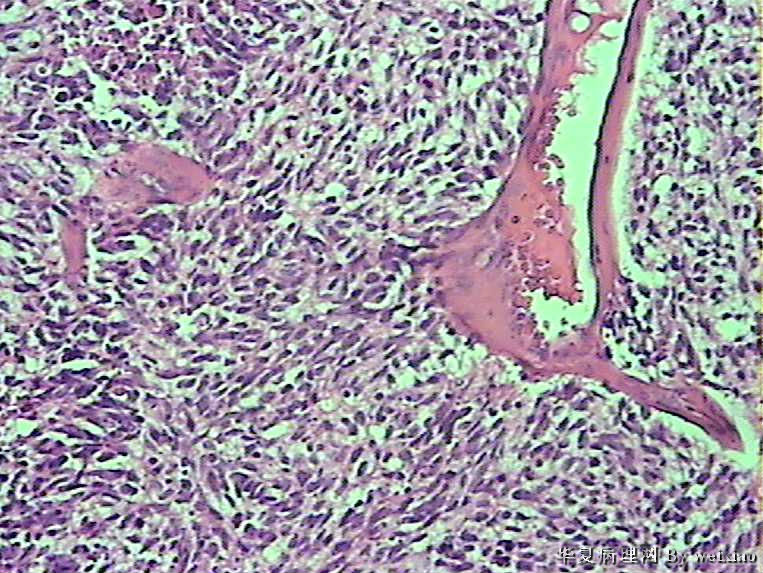

病史:男45岁,头痛2个月,手术所见:额叶占位性病变,与周围正常脑组  织的界限不清。

大体:灰白色碎组织一堆,质软,大小:2.5*1.8*1.3cm

• 额叶肿瘤图1

图1

×参考诊断

胶质母细胞瘤

坏死+细胞密度+异性+围绕血管现象。

考虑血管外皮瘤

脑膜瘤,查看核分裂和肿瘤侵犯程度。

不典型脑膜瘤

血管外皮瘤,SFT.

会诊胶质母细胞瘤

The tumor cells are kind of spindle, need to rule out gliosarcoma, you need to check MRI films, do immunostain for GFAP, and vimentin. The vascular proliferation (VP) supports GBM.

肿瘤细胞呈梭形,血管增生明显,有坏死,符合胶质母。